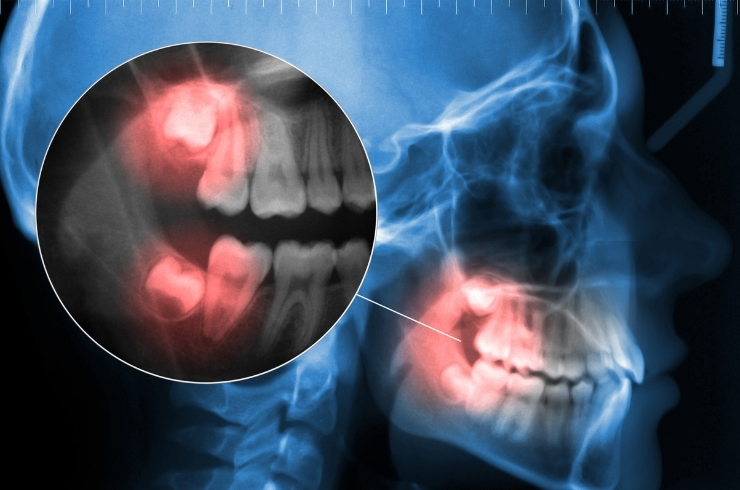

Safe extraction of impacted or problematic wisdom teeth to prevent pain, infection, and alignment issues.

Safe, painless removal of decayed, damaged, or problematic teeth to prevent infection, pain, and maintain overall oral health and comfort.

Relieves tooth pain by removing infected pulp, disinfecting the tooth, and restoring function with long-term protection.